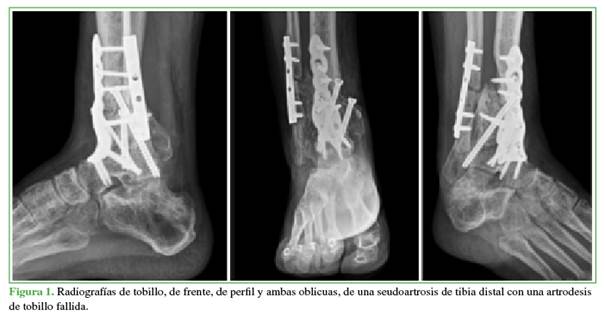

A los 11 meses de la cirugía, las radiografías revelaron una fatiga de la placa tibial, asociada a seudoartrosis tibioastragalina y, en el examen físico, se detectó movilidad en el sitio de fusión (Figura 1).

Se solicitaron análisis de laboratorio completos y los resultados estaban dentro de los valores normales: glóbulos blancos 8500/mm3 (valor normal: 4000-10.000/mm3), proteína C reactiva 0,9 mg/dl (valor normal: 0,8-1,2 mg/dl) y velocidad de sedimentación globular 12 mm (valor normal: 8-20 mm).

Se optó por una revisión en dos tiempos según los principios de Masquelet, ante la sospecha de infección, debido a la falta de consolidación, asociada a la fatiga del implante y la persistencia del dolor.